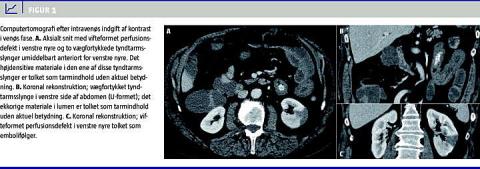

Fem dage efter konverteringen blev patienten indlagt med stærke abdominalsmerter, opkastninger og blodig afføring. Biokemi viste forhøjede infektionstal, normal trombocytkoncentration, international normalized ratio (INR) 1,3, alaninaminotransferasekoncentration 109 U/l og laktatdehydrogenasekoncentration 727 U/l. En computertomografi (CT) af abdomen (Figur 1 ) viste tegn på tyndtarmssubileus, vægfortykkelse af den proksimale jejunum og et hypodenst område i venstre nyre. En magnetisk resonans-skanning på dag 7 viste fri væske i abdomen.